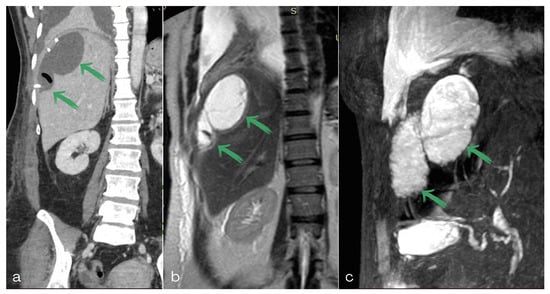

2. Case Report